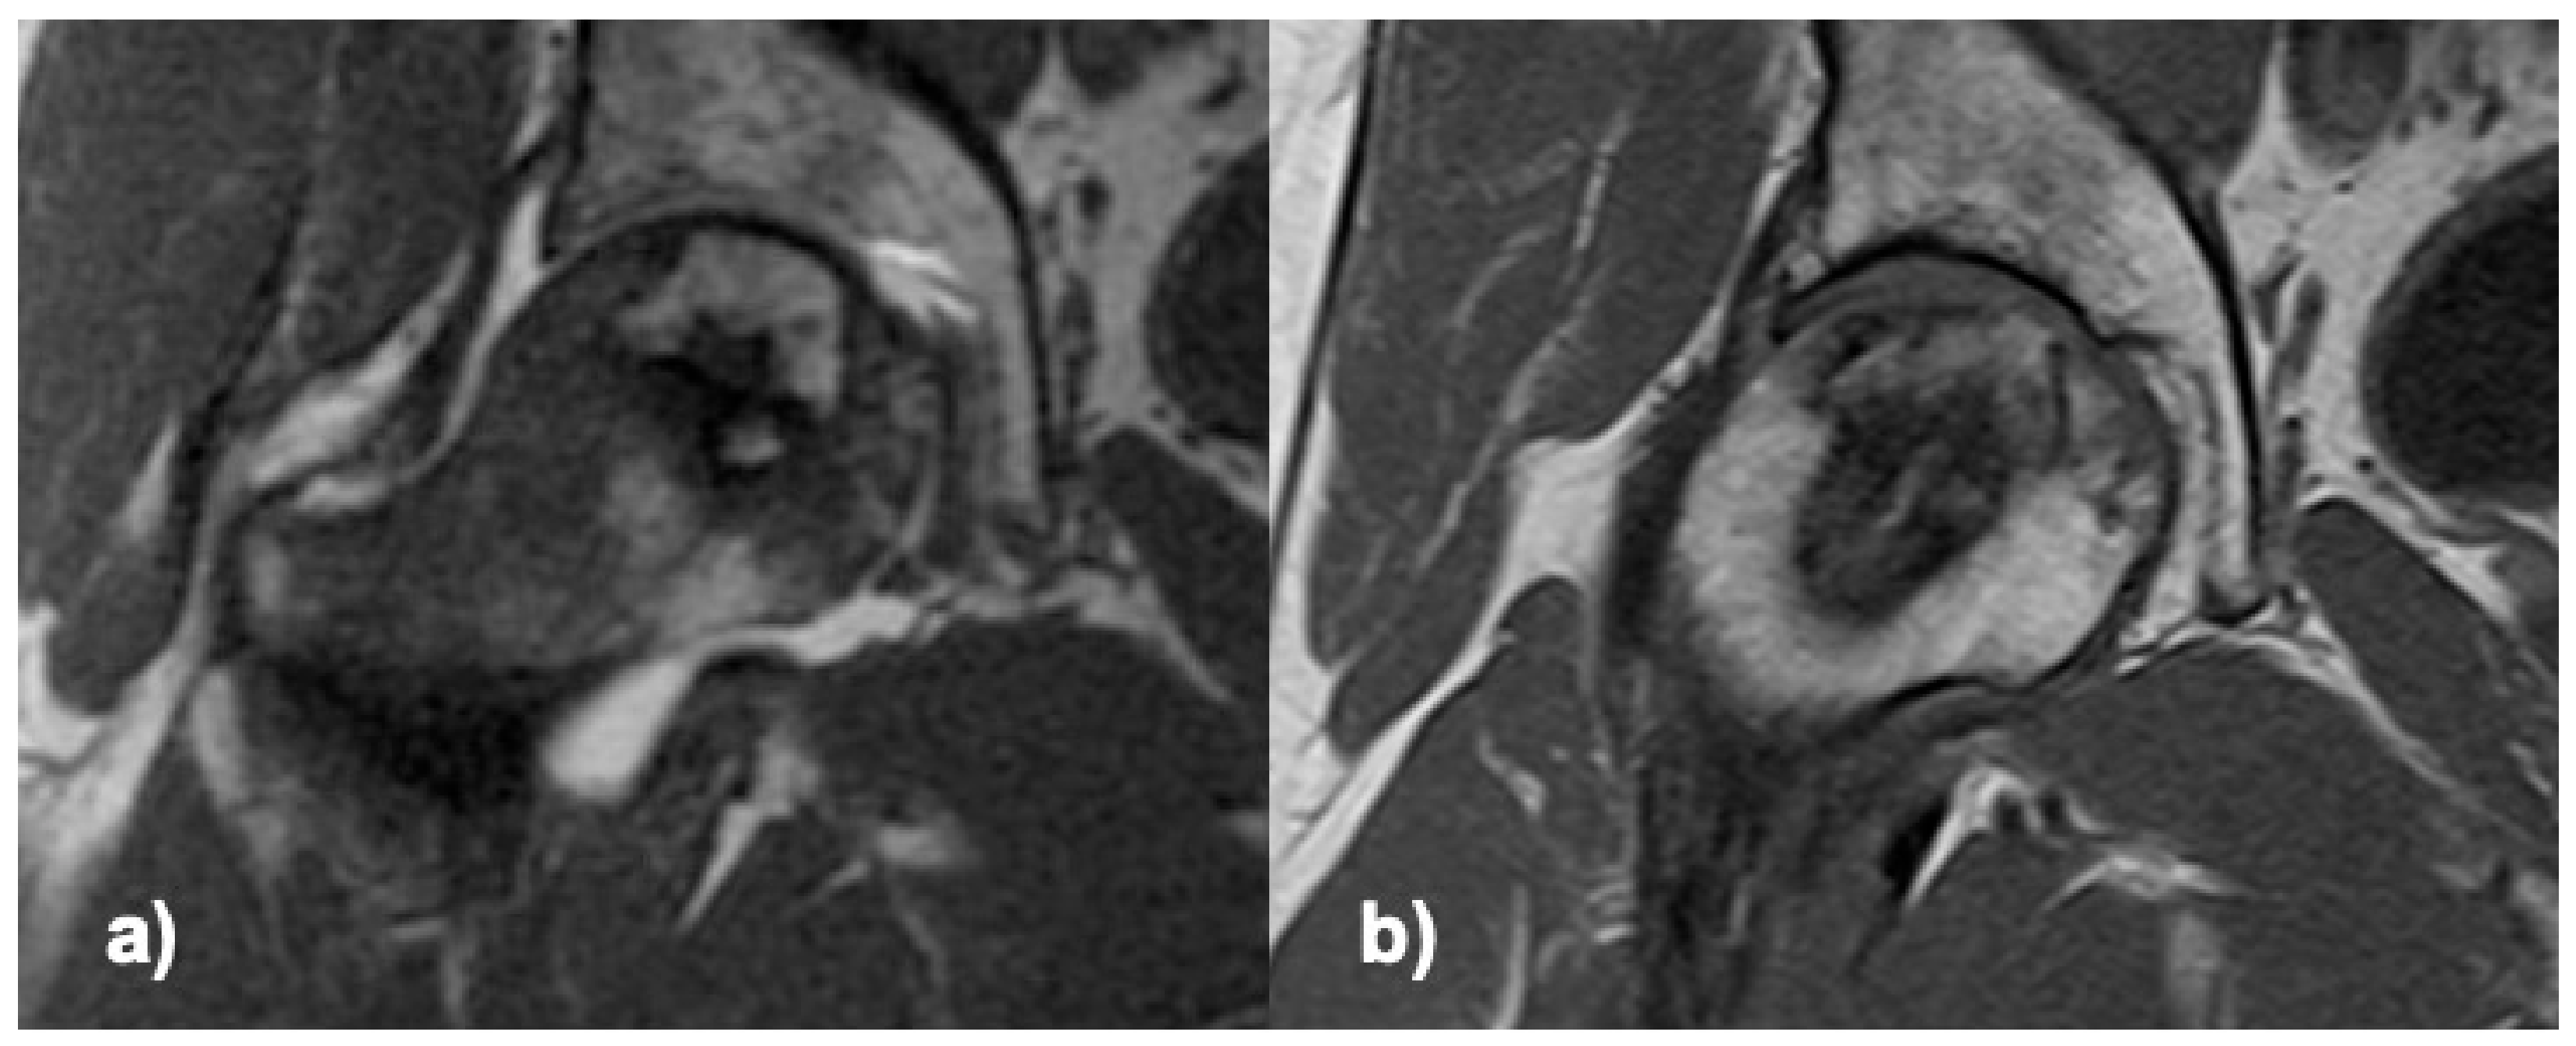

Clinical and radiological regeneration (Figure 2), with maintained head sphericity, was observed in 80% of the treated patients (16/20) after a one-year follow-up, 73% (16/22) on ITT (including 2 drop-out cases only evaluated at 3 months). Four cases progressed to the next stage of ON (4/20), and of these, 3 received THR. Generalized estimating equation analysis (model adjustment: Wald Chi-square = 177.35; p = 0.001) for pain higher than 30/100, age higher than 50, time since diagnosis higher than 3 months, positive alcohol consumption, and positive smoking habit, only showed a significant interaction of ON progression/THR with pain (OR = 3.8 [3.0–4.7]; p = 0.001).

Figure 2.

T1 MRI of the femoral head, coronal section through the ON area; (a) preoperative, (b) 6 months after delivering the cells.